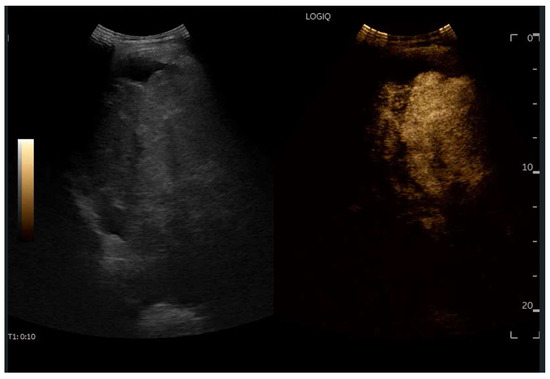

Abdominal ultrasound is a fundamental diagnostic tool in clinical practice, due to its availability, safety, and overall accuracy. This Special Issue will delve into the most recent technological and methodological innovations in abdominal ultrasound imaging, offering readers a comprehensive overview of advanced techniques, specific clinical indications, and solutions to emerging challenges. Among the various topics, it will cover the use of high-resolution probes, the integration of elastography for assessing liver fibrosis, and the application of contrast-enhanced ultrasound for identifying complex lesions. Strategies for training and professional development will also be examined to improve ultrasound performance and result interpretation.

- CEUS